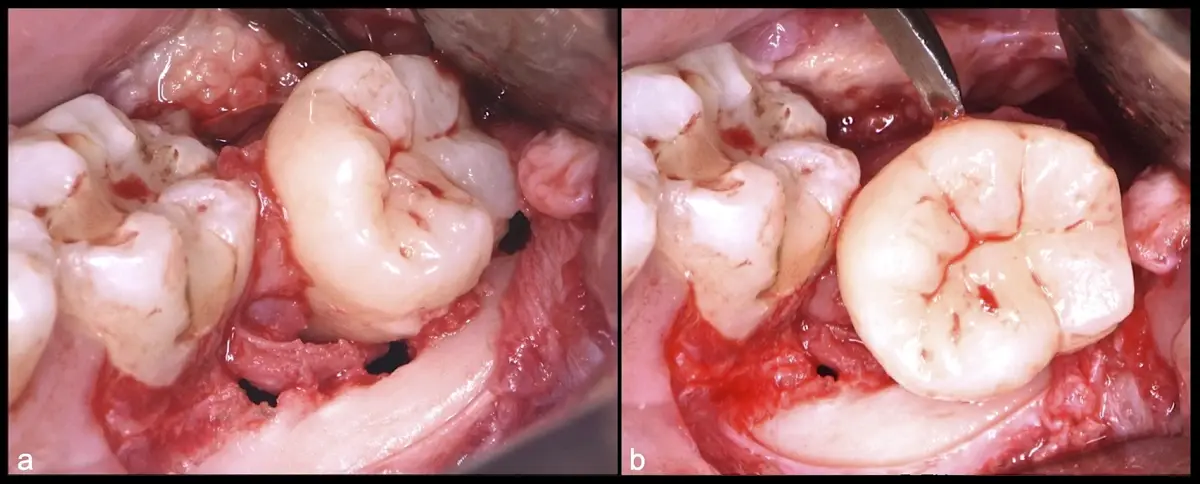

El procedimiento puede variar en su complejidad dependiendo de su ubicación, profundidad, angulación, y la densidad ósea circundante.2 Uno de los pasos más críticos y cruciales en la extracción es la osteotomía previa y concomitante al acceso quirúrgico del diente, para lo cual se utilizan diversos instrumentos como cinceles y martillos, instrumental rotatorio o de corte por ultrasonido.3

Estos pueden ser de carácter altamente invasivo, lo que implica riesgo de lesión en tejidos blandos y óseos, y con una consecuente reacción inflamatoria significativa. Suelen estar acompañadas de síntomas postoperatorios como dolor, edema y apertura bucal limitada en casos de espasmo muscular a causa de la manipulación de los maxilares.4

El instrumento piezoeléctrico utiliza un corte micrométrico que retira un área de superficie mínima de hueso, y reduce el riesgo de termonecrosis marginal en comparación con las fresas rotatorias convencionales.

En contraste, el instrumento piezoeléctrico utiliza un corte micrométrico que retira un área de superficie mínima de hueso, y reduce el riesgo de termonecrosis marginal en comparación con las fresas rotatorias convencionales.9 Los micromovimientos mejoran la precisión en el corte y el control táctil, y eliminan las macrovibraciones que se producen con los instrumentos rotatorios.10 Su frecuencia de oscilación es la amplitud de 60-200 μm horizontalmente y de 20-60 μm en sentido vertical, lo que es muy inferior en comparación con las micro sierras oscilantes; por lo tanto, proporciona cortes de osteotomía precisos y seguros. Adicionalmente, posee vibraciones ultrasónicas que descomponen el líquido de irrigación en partículas muy pequeñas (fenómeno de cavitación, que produce un efecto hemostático y así reduce la pérdida de sangre), lo que proporciona una visión clara y sin obstáculos del campo quirúrgico11,12.